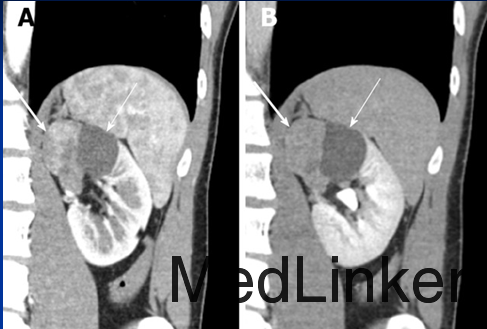

查体:左肾区叩痛(+),腹部无明显压痛、反跳痛,余未见明显异常。 辅查:我院腹部CT平扫+增强示:左肾囊实性肿块,大小约68X42mm,实性部分增强后在皮髓质期明显强化,后强化减低,囊性部分未见明显强化,考虑左肾恶性肿瘤并囊性变。余实验室检查未见明显异常。

入院诊断:左肾肿物:左肾癌?入院后行左肾肿物切除术,术中见一类球星肿物位于左肾下极,大小约6x5x4cm,颜色较正常肾实质深,质韧,表面较光滑,边界尚清晰,无明显粘连。术后病理示:(左肾盂旁肿物)肾类癌。